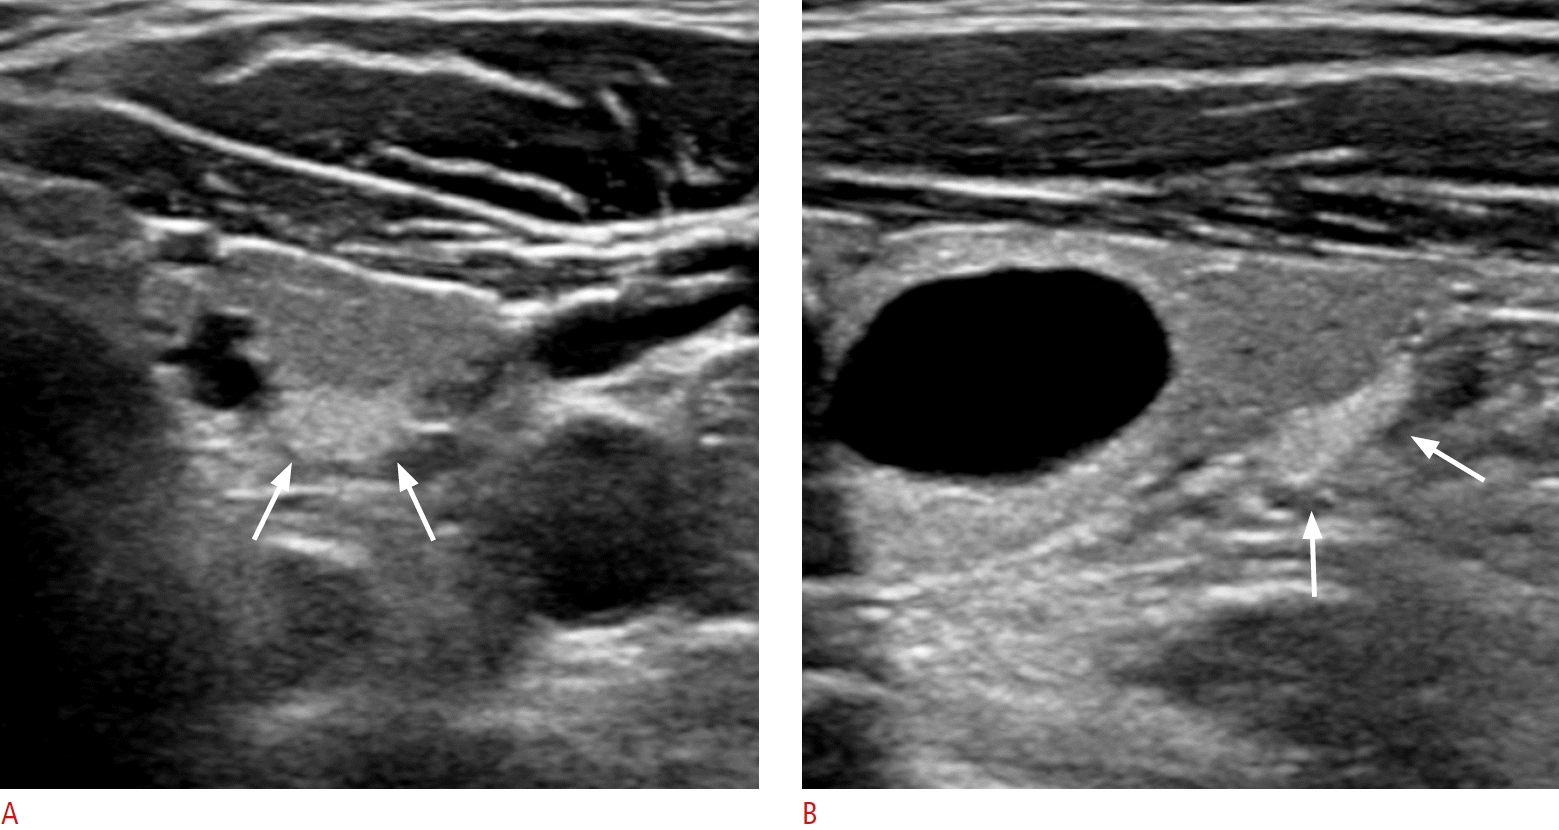

Fig. 6.

Metastatic lymph nodes with mild hyperechogenicity from papillary thyroid carcinomas.

A. A transverse image shows a lymph node (arrows) that is slightly hyperechoic compared to the neck muscle at the pretracheal midline central neck (level VI) in a 63-year-old female patient. The lymph node shows an ovoid shape on the longitudinal image (long axis/short axis ratio, 1.8) (not shown). It does not show echogenic foci or a cystic change. The metastatic lymph node was diagnosed by fine needle aspiration and surgery. B. A transverse image shows an ovoid, mildly hyperechoic lymph node in the left infrathyroid paramedian central neck (level VI) in a 42-year-old female patient. The lymph node shows echogenic foci (arrows). The shape was ovoid on the longitudinal image (long axis/short axis ratio, 2) (not shown). The metastatic lymph node was diagnosed by surgery.